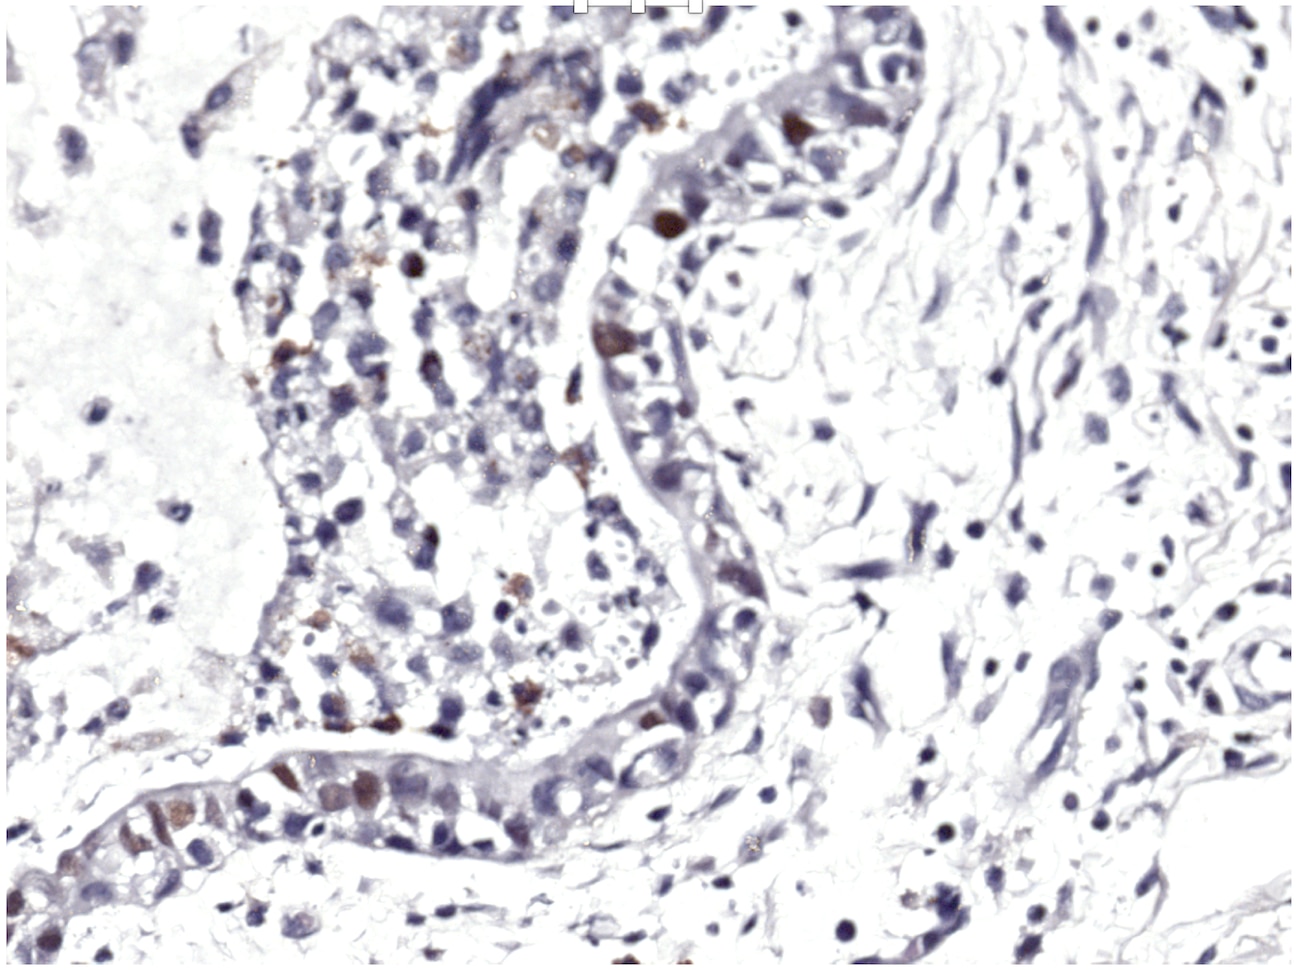

p21/CIP1/CDKN1A in Human Breast Cancer Tissue. p21/CIP1/CDKN1A was detected in immersion fixed paraffin-embedded sections of human breast cancer tissue using 1.7 µg/mL Goat Anti-Human p21/CIP1/CDKN1A Antigen Affinity-purified Polyclonal Antibody (Catalog # AF1047) overnight at 4 °C. Tissue was stained with the Anti-Goat HRP-DAB Cell & Tissue Staining Kit (brown; Catalog # CTS008) and counterstained with hematoxylin (blue). View our protocol for Chromogenic IHC Staining of Paraffin-embedded Tissue Sections.